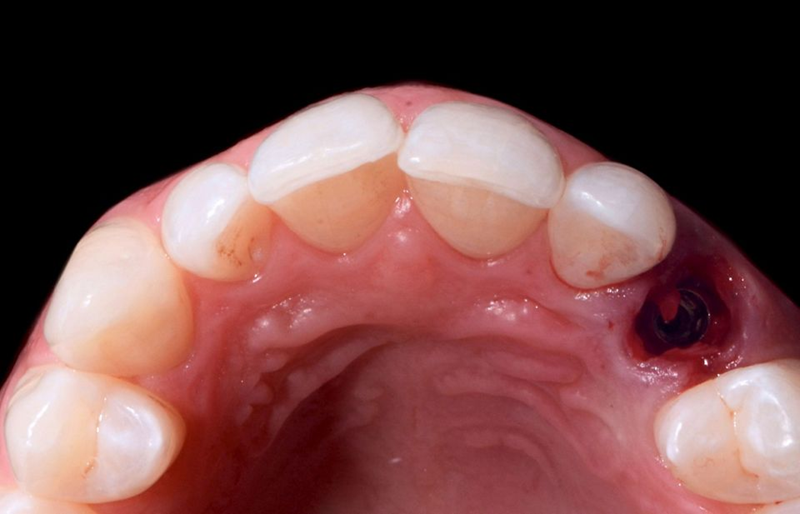

种植体在准备好的骨位点上以完美的引导接合到套管中(图 37),专用的 BLX® 转移件将种植体驱动到正确的位置(图 38)。种植体植入和移除导板后的咬合视图显示了最佳的 3D 种植体位置(图 39)。

Fig. 39: Occlusal view after the implant placement and the removal of the...

尽管可用骨量减少,但种植体稳定性仍可能达到 35n/cm 的扭矩值,这使得可以立即放置假体(图 40)。将直径为 3.8 毫米、牙龈高度为 1.5 毫米的定制临时基台用螺钉固定在种植体顶部(图 41)。然后,用棉球保护临时基台的烟囱,以避免在后续步骤中堵塞螺钉的入口。然后将临时牙冠放入透明面罩内;在用树脂填充牙冠后,通过透明面罩将其固定到位,以便与临时基台连接。树脂聚合后,拧下临时牙冠(图 42),牙冠和基台之间的空间填充树脂,然后进行调整,直到获得适当的紧急轮廓(图 43)。